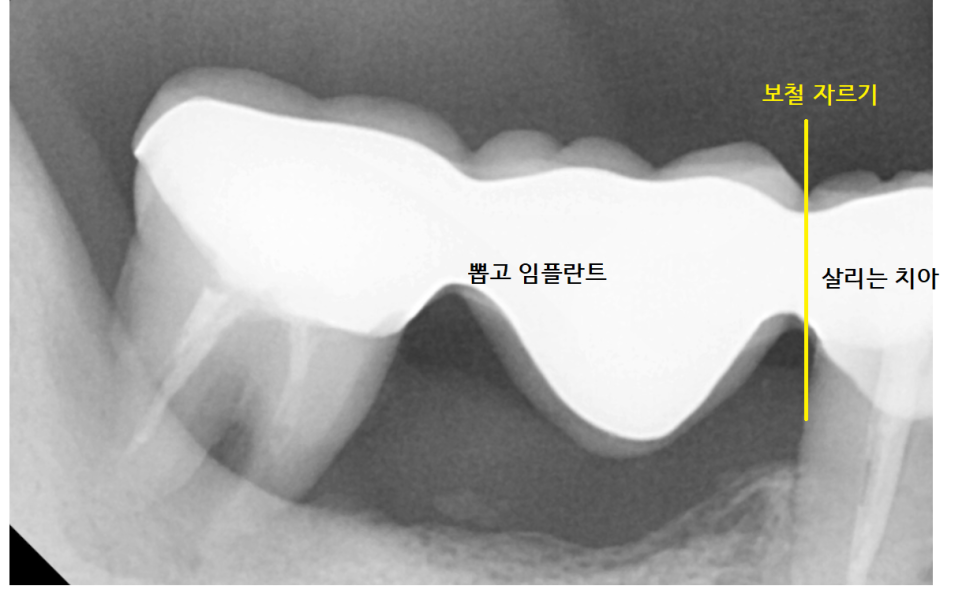

3개의 보철 중

작은 어금니 치아는 살려볼 수 있었는데요.

자연 치아가 1개라도 더 있으면 유리하기 때문에

오래된 브릿지를 잘라서

부분 임플란트 하기로 상담해 드렸습니다.

결국 브릿지 연결되어 있던 것을 잘라서

앞에 치아는 살리고

뒤에 치아는 뽑는 것으로

강일역 치과에서 임플란트를 진행했습니다.